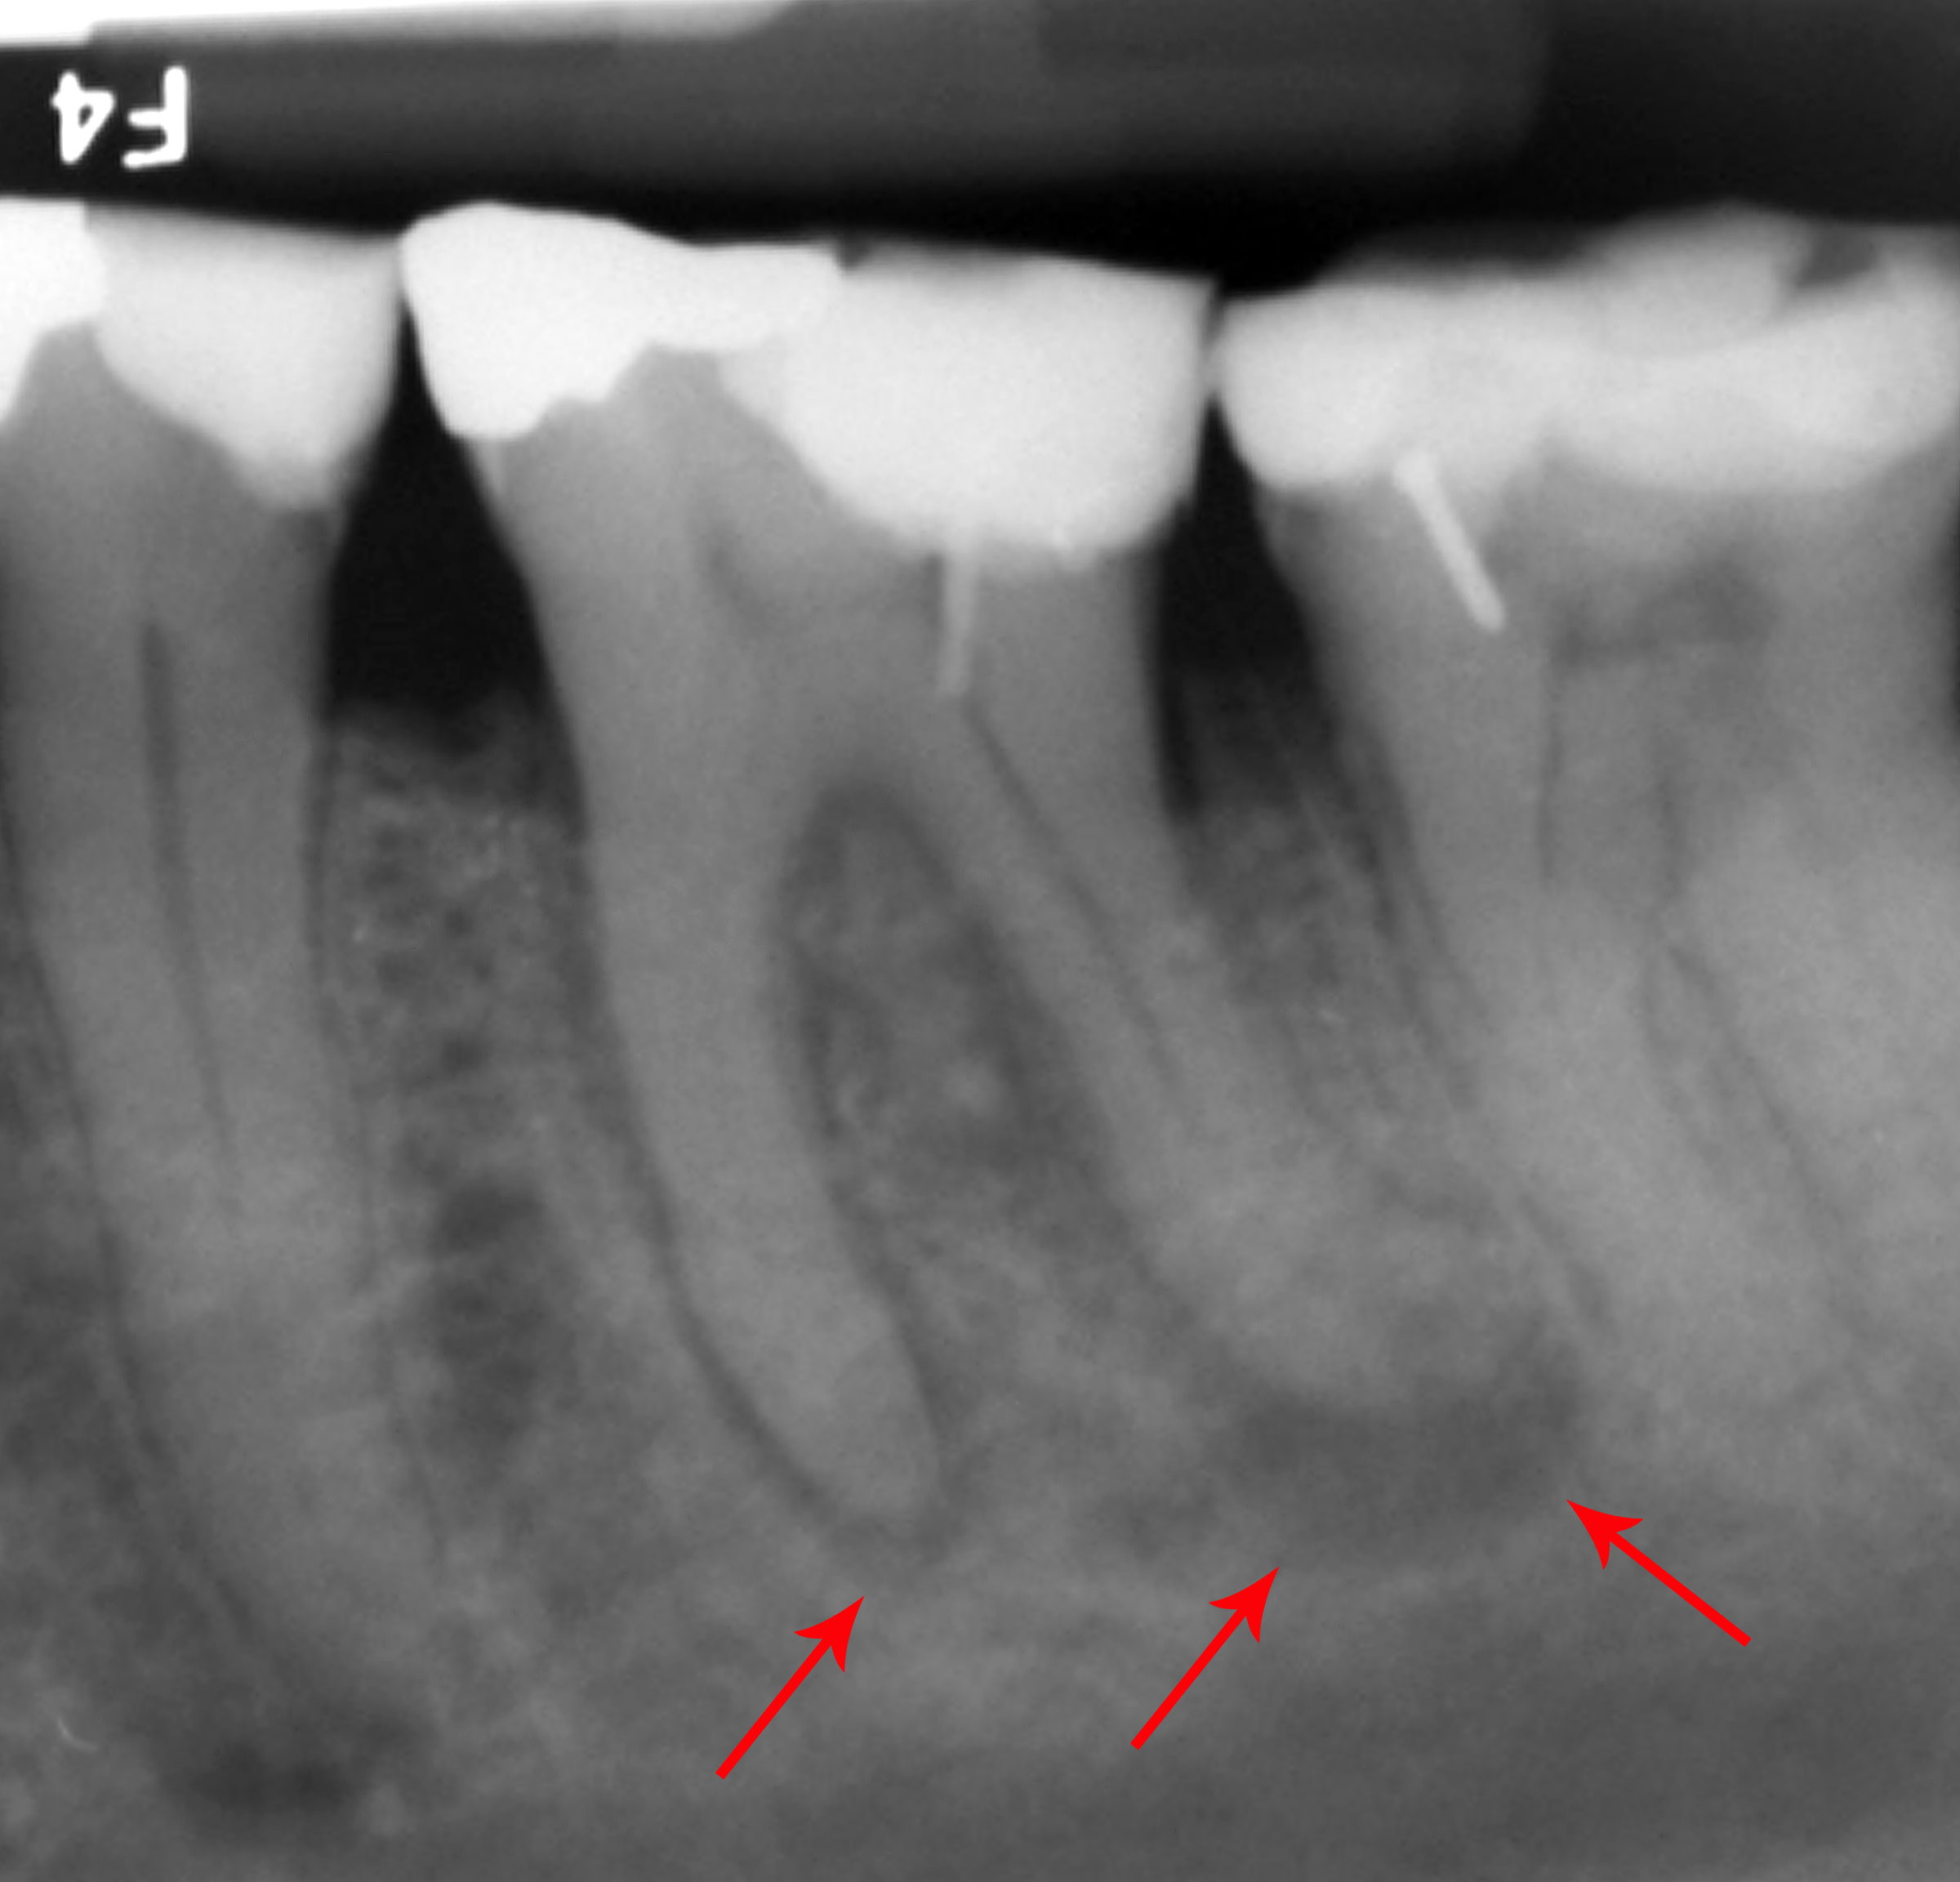

X-ray explanation of bad root canal therapy

조잡한 근관 치료의 엑스레이 사진

근관 치료의 또 다른 흔한 합병증은 근관 전체를 완전히 깨끗하게 청소하고 근관 충전재(보통 거타퍼차)로 채우지 못했을 때 발생한다. 반면에, 근관 충전재가 치근단에서 밀려나와 다른 합병증을 유발할 수도 있다. 위 그림의 엑스레이는 잘못된 근관 치료를 받은 인접한 두 개의 치아를 보여준다. 근관 충전재(3, 4 및 10)는 치아 뿌리(5, 6 및 11) 끝까지 확장되지 않는다. 치아 뿌리 하단의 어두운 원(7 및 8)은 주변 뼈의 감염을 나타낸다. 권장되는 치료법은 근관 치료를 다시 하거나 치아를 발치하고 임플란트를 식립하는 것이다. 불량한 품질의 충전재 또는 밀봉재도 근관 치료 실패의 원인이 될 수 있다.[46]

근관 치료를 받은 치아는 치과의사가 치아 내 모든 근관을 찾아서 세척하고 충전하지 못하는 경우와 같이 치유에 실패할 수 있다. 상악 어금니의 경우, 치아에 3개가 아닌 4개의 근관이 있을 확률이 50% 이상이지만, 종종 "근심 협측 2"라고 불리는 네 번째 근관은 보기가 매우 어렵고, 이를 보기 위해서는 특수 기구와 확대경이 필요한 경우가 많다(가장 흔하게 첫 번째 상악 어금니에서 발견된다. 연구에 따르면 이러한 치아의 평균 76%에서 최대 96%가 MB2 근관을 가지고 있다). 이 감염된 근관은 지속적인 감염이나 치아의 "악화"를 유발할 수 있다.